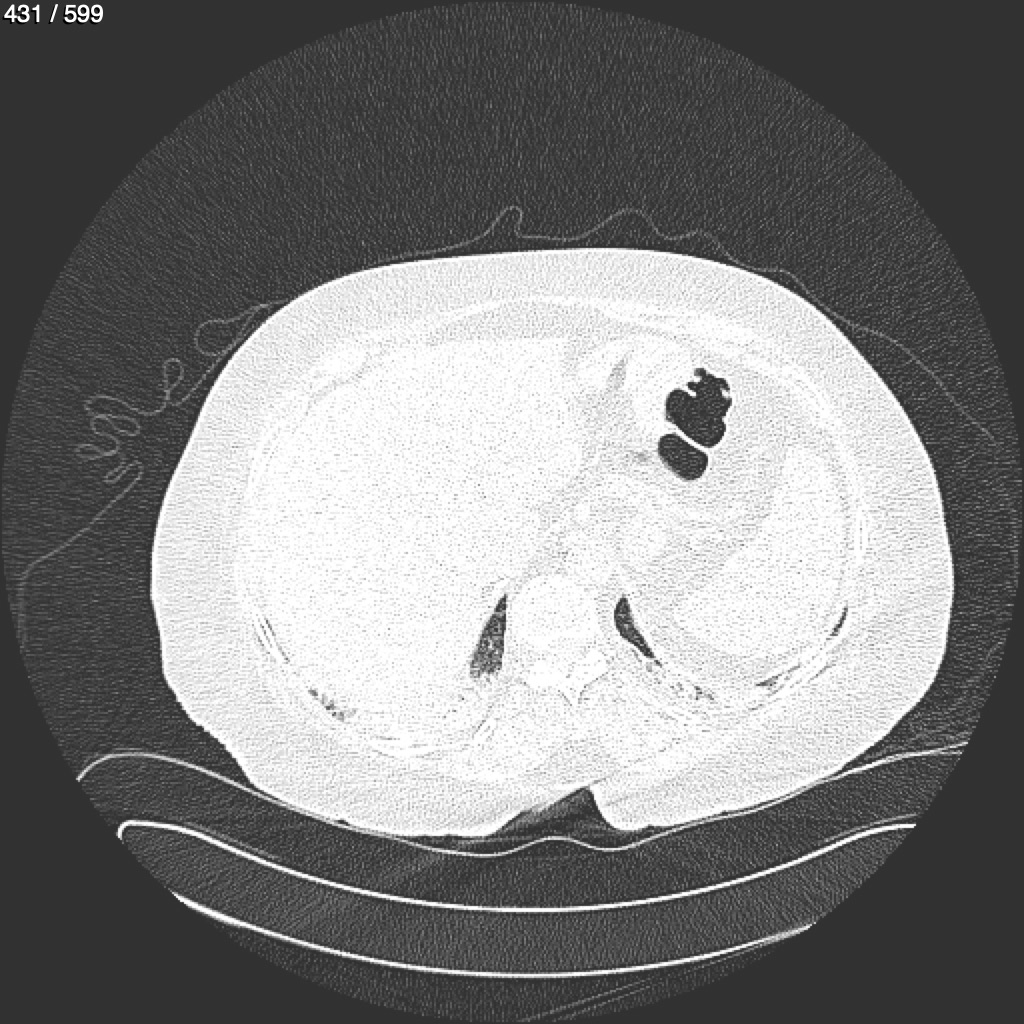

Home G​l​o​r​i​a​ ​G​l​a​d​y​s​ ​B​e​a​s​l​e​y​ ​-​ ​T​ó​r​a​x​ ​T​o​r​a​x​_​S​i​m​p​l​e​ ​(​A​d​u​l​t​o​)